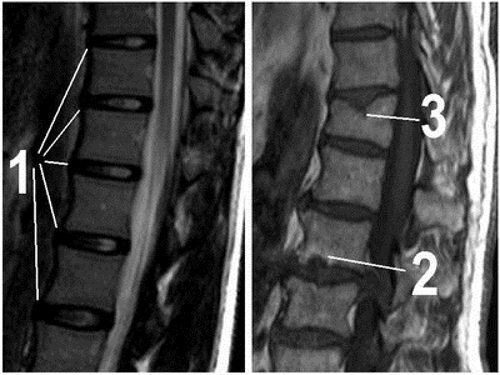

Диагностика остеохондроза позвоночника с корешковым синдромом включает несколько медицинских обследований. Врач проводит осмотр пациента, собирает анамнез и анализирует основные жалобы. Для уточнения диагноза выполняется рентгенография позвоночного столба в передней и задней проекциях. Если имеются осложнения или неясная причина заболевания, пациента направляют на магнитно-резонансную томографию.